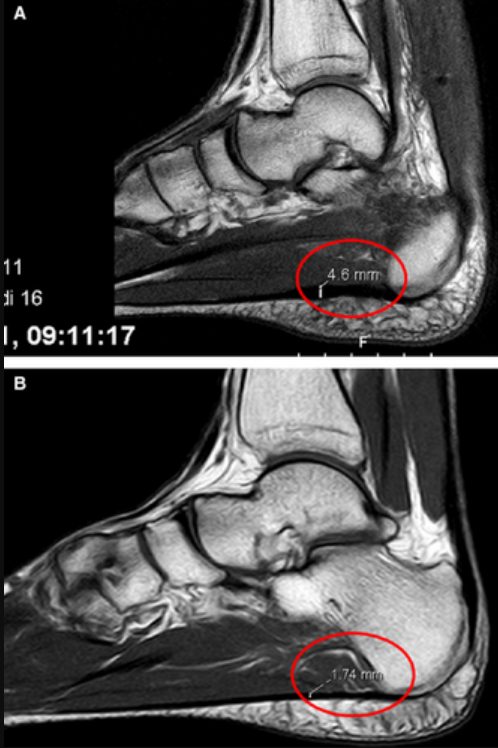

МРТ. Резервирована для атипичных случаев и дифференциальной диагностики. Выявляет утолщение фасции, повышение сигнала в Т2-режиме, перифасциальный отёк, а также позволяет исключить стресс-перелом, опухоли и нейропатии. Показана при подозрении на разрыв подошвенной фасции (острая боль после инъекции ГКС или травмы).

Рис. 5. МРТ: А — пациент с подошвенным фасциитом (утолщение фасции, повышение сигнала), В — здоровый пациент